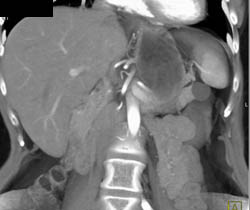

Diagnosis

Cystadenoma